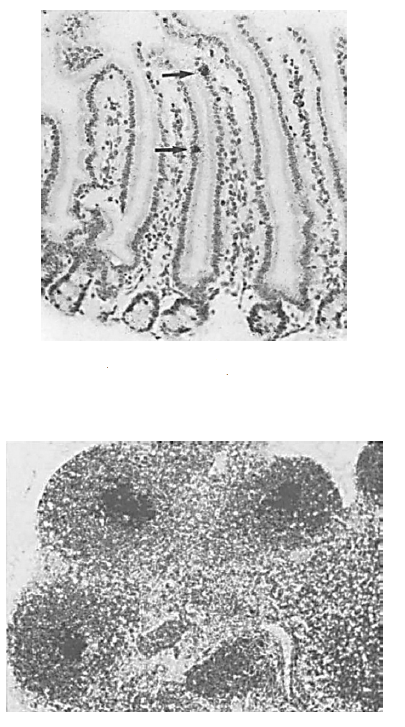

Intranuclear adenoviral inclusions in SI of infant mouse

Vacuolated enterocytes (typical of normal neonatal mouse bowel)

Amphophilic, intranuclear inclusions in intestinal epithelium (distal SI)